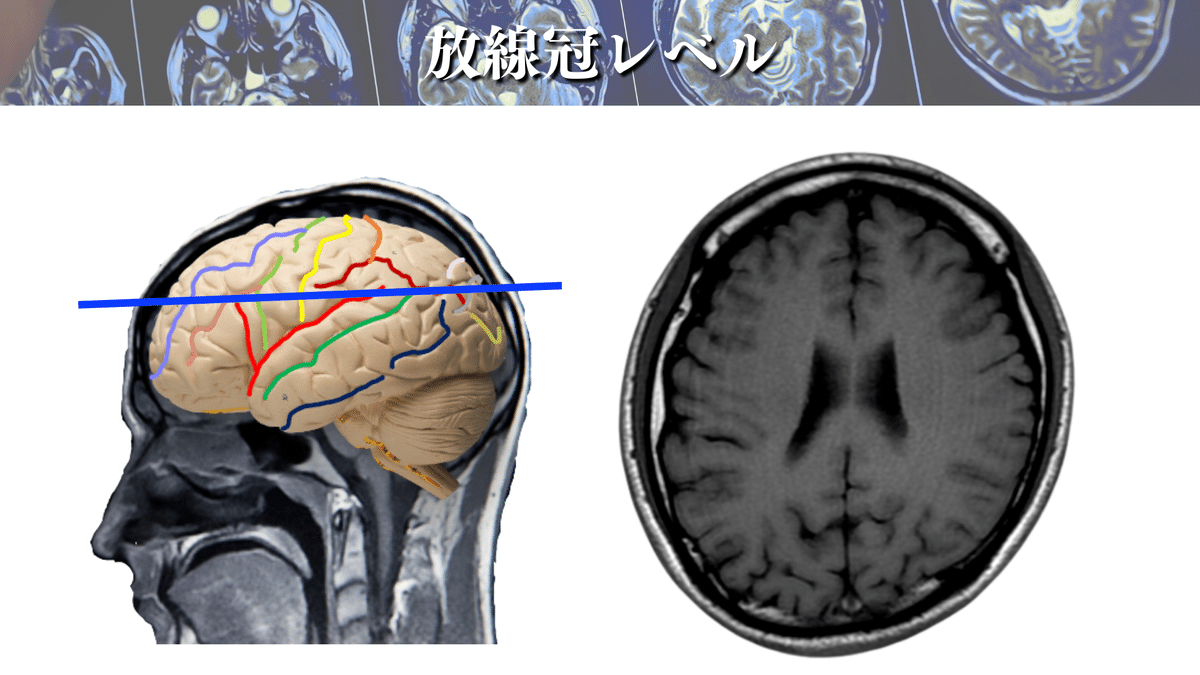

放線冠レベル

このレベルはよく養成校でも解説されるのではないでしょうか🤔?

まずは大まかにCSTに走行を見ていきましょう👀

上図のような場所をCSTは走行していきます🏃♀️

ポイントとしては、側脳室(体部)の真ん中に線を引いて、線よりも下側をCSTが走行するイメージです☝️